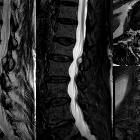

Facettengelenkszyste LWS

mit Facettengelenks-Zyste von rechts nach intraspinal mit hochgradiger spinaler Enge.

Intraspinale,

epidurale, eingeblutete Synovialzyste Facettengelenk mit akuter Klinik mit Schmerz und Kaudasymptomatik. Oben sagittal T1 nativ (hell !), T2, STIR, unten T2 axial , T1 KM FS axial und sagittal.